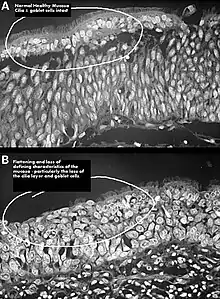

| Altered nasal anatomy after bilateral subtotal inferior turbinectomy, the removal of most turbinate tissue. | |